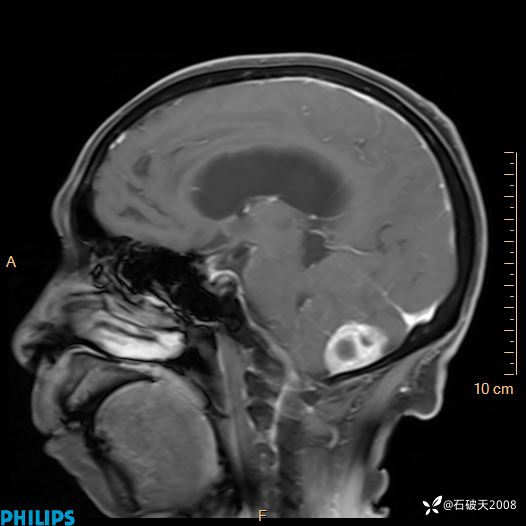

增强矢状位